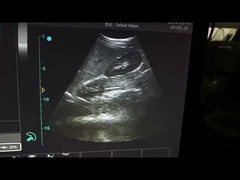

Kwaliteit Draagbare ultrasone Scanner, handbediende Ultrasone klankscanner Fabrikant uit China

Alle video's